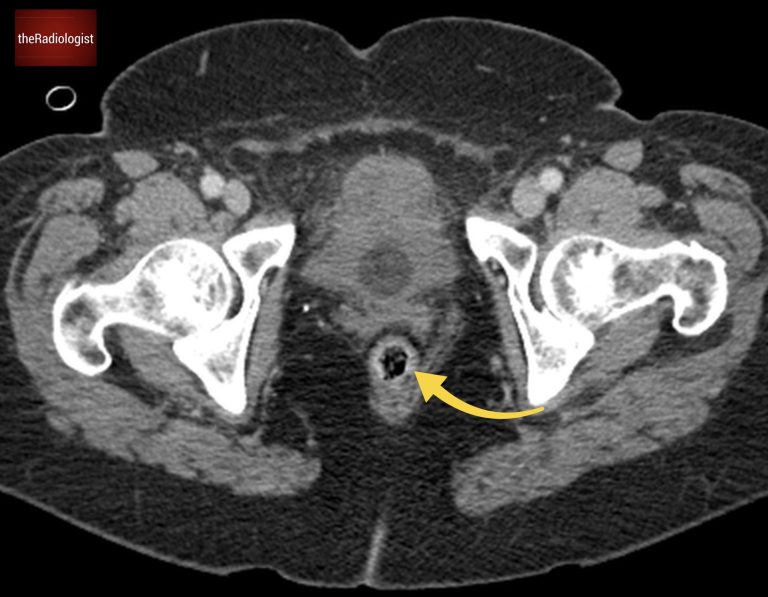

Now let’s look at the CT scan. I like to follow the large bowel from the rectum and follow it up. If you do so in this case you will find the whole of the large bowel is not dilated and normal in calibre, essentially excluding large bowel obstruction.

Go to the bottom of the scan and find the rectum then follow the colon all the way round.

Now looking elsewhere we can see fluid filled dilated bowel loops – these are small bowel loops. There are however other loops of small bowel which are not dilated. This implies mechanical small bowel obstruction – here we are looking for dilated small bowel proximal to collapsed small bowel with a sharp transition point between the two.

It is now a case of following the small bowel and looking for a transition point between dilated and collapsed small bowel. I like to start from the stomach and follow the small bowel round. If you do so eventually you will come across a transition point within the right side of the abdomen from dilated small bowel to collapsed small bowel.

Find this small bowel loop on the right side of the abdomen. Once you follow this you will find it leads to a transition point where distal to this there are only collapsed small bowel loops.